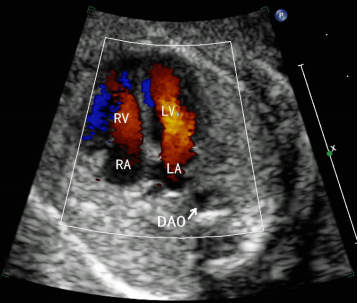

| 显示结构 | 脊柱、降主动脉、左心房、左心室、右心房、右心室、二尖瓣、三尖瓣、房间隔、卵圆孔及卵圆孔瓣、室间隔、肺静脉 |

| 观察内容 | 1、 心脏位于胸腔内,2/3位于左侧胸腔,1/3位于右侧胸腔,心脏长轴指向左侧并成角,平均为(45±20)°。心脏占胸腔面积约1/3。 |

| 2、 左心房离脊柱最近,与降主动脉位于同侧,左心房顶部有左、右肺静脉开口;左、右心房内径大致相等,其间为房间隔,可见卵圆孔及卵圆孔瓣朝左心房飘动。 | |

| 3、 心脏中央“十”字交叉结构存在,左房、室间为二尖瓣,右房、室间为三尖瓣,三尖瓣附着点更接近心尖部,两组房室瓣启闭活动自如;左心室腔内壁较光整,右心室腔呈三角形,内壁粗糙,并可见回声稍强的调节束。左、右心室横径接近或右心室稍大于左心室,两者之间为室间隔,室间隔回声无明显中断。 | |

| 4、 心包腔内无明显积液。 | |

| 5、 CDFI显示舒张期两侧房室瓣血流束宽度基本相等,收缩期无明显反流,卵圆孔处分流方向及宽度正常,室间隔无明显异常穿隔血流。 | |

| 6、 CDFI显示至少一支肺静脉汇入左心房。 | |

| 7、 胎儿心率及心律无明显异常。 | |

| (图4-6) | |

![]() | ![]() |

图4 胎儿心尖四腔心观二维显像 | 图5 胎儿心尖四腔心观彩色多普勒显像 |

| 注:LV:左心室;LA:左心房;RV:右心室;RA:右心房;DAO:降主动脉;FO:卵圆孔; PV:肺静脉 | |